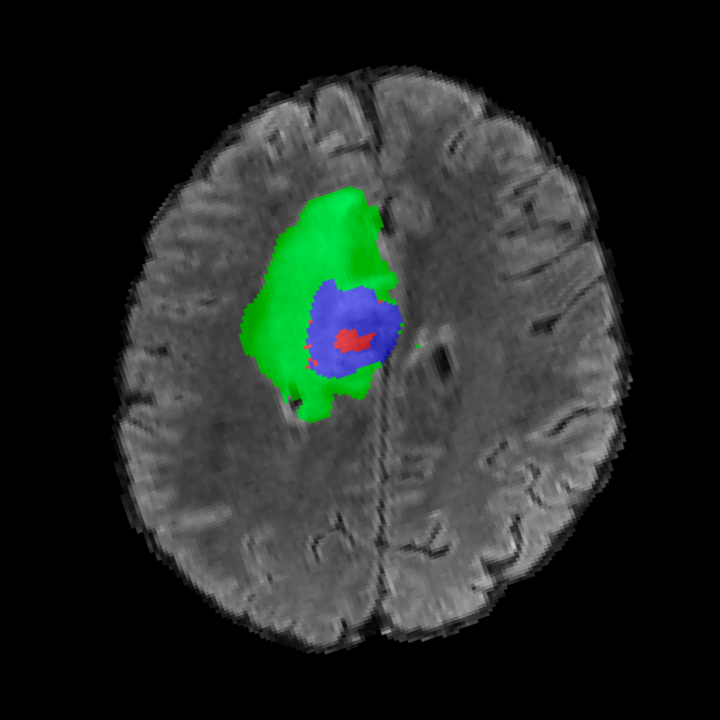

BRATS. The largest public dataset of brain tumours consisting of 5,880 MRI scans from 1,470 brain diffuse glioma patients, and corresponding annotations of tumours[4, 45, 5]. All scans were skull-stripped and resampled to 1 mm isotropic resolution. All images have a resolution of 240 240 155, and we use the flair T2 sequence. Tumours are annotated for 3 classes: Whole Tumour (WT), Tumour Core (TC), and Enhanced Tumour Core (ET).

Tumour Information Preservation. For the brain tumor segmentation, we use a Swin UNETR model[28, 70], trained with random rotation, and intensity as data augmentation. On the test set with human ground-truth annotations (), the brain volumes generated from single slice input preserve the volume of the different tumour components (paired t-test, for all 3 classes). In Figure 4, we highlight the tumor profiles of the generated MRIs compared to the ground truth tumour profile. The real MRI Dice score in the test set is 85.15 while the generated MRIs from a single slice have a dice score of 83.09. This shows how the generated MRIs indeed preserve the tumor information and can act as an affordable and informative pseudo-MRI, before conducting an actual costly MRI examination in hospitals. More detailed results are provided in supplementary material.